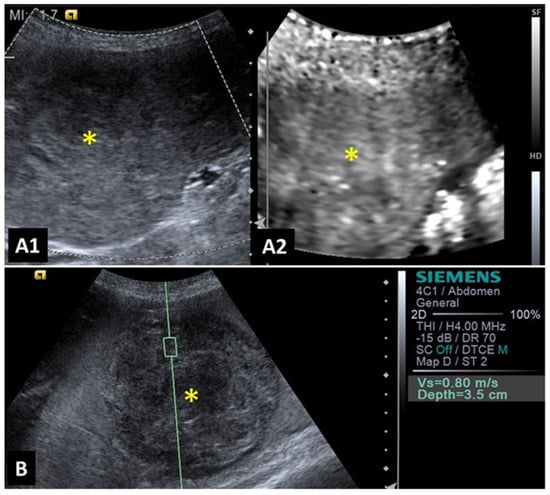

2.1. Mammary Glands

2.3. Spleen

2.5. Liver